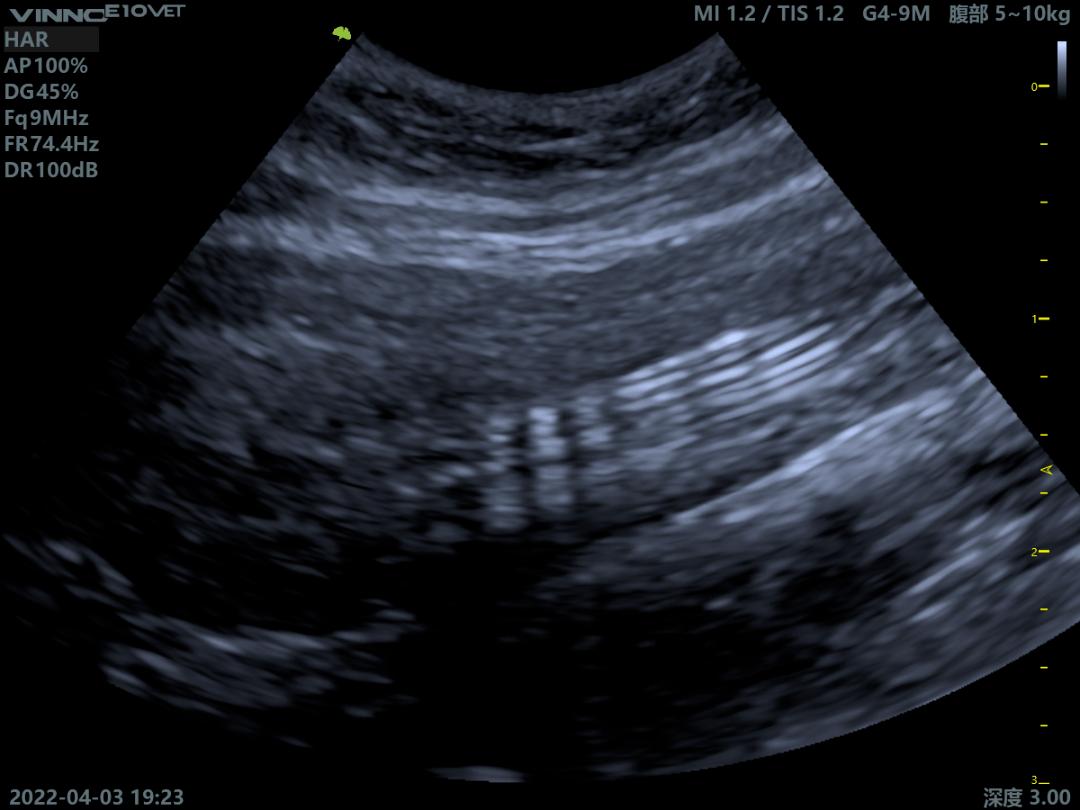

就诊时发现尿道口已闭合,膀胱壁增厚,且内有强回声物质,尿检大量炎性细胞且有吞噬细菌